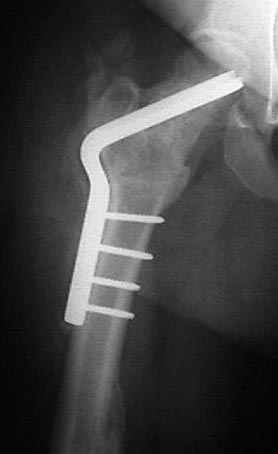

Если, например, доводится лечить больных с псевдартрозами шейки бедра, то надобность есть, и приходится. См. приложение.

На рисунке N1 предоперационный план лечения ложного сустава шейки бедра- линия ложного сустава, угол и направление введения импланта, клиновидная остеотомия в градусах и миллиметрах, второй снимок после коррекции, расчет, на сколько удлиняется конечность и размеры импланта;

N3 рисунок окончательный снимок, после операции моя рентгенограмма должен выглядеть примерно как эта картина. На N4 снимке клин перед удалением; N5 послеоперации 3 нед.; N6 окончательная рентгенограмма.

(доложен в Ст. Петербурге 2003 и в Москве 2004)

варус при проксимальном отделе 95 градусной пластиной.